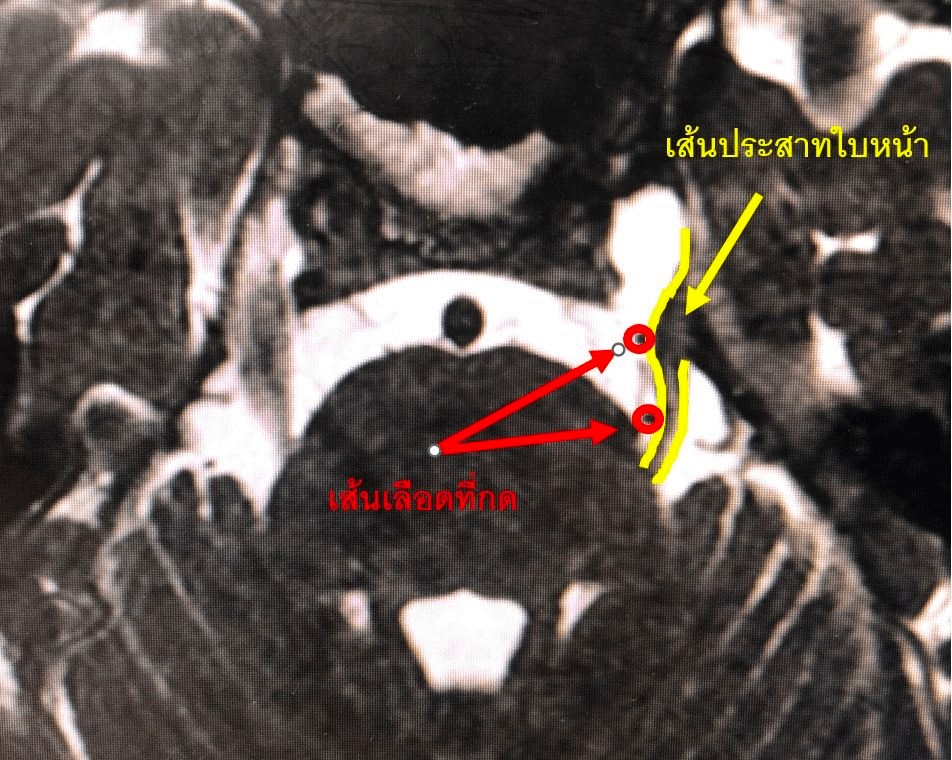

สาเหตุของโรคปวดเส้นประสาทใบหน้าเกิดได้จากหลายสาเหตุ แต่ที่พบบ่อยที่สุดคือเกิดจากเส้นเลือดสมองที่มีความโค้งไปกดบริเวณเส้นประสาทรับความรู้สึกใบหน้า ดังนั้นการรักษาที่เป็นการแก้ไขสาเหตุคือ การผ่าตัดเพื่อแยกเส้นเลือดออกจากเส้นประสาท (Microvascular decompression) ซึ่งหากทำได้ผลผู้ป่วยจะหายปวดได้ทันทีและเนื่องจากไม่มีการทำลายเส้นประสาทผู้ป่วยจึงไม่เกิดอาการชาหลังผ่าตัด (ในขณะที่การรักษาด้วยยาจะไม่หายขาด และการรักษาโดยการทำลายเส้นประสาทจะทำให้เกิดอาการชาใบหน้าตามมา)

สำหรับผู้ป่วยรายนี้เมื่อให้คำแนะนำแล้ว คุณลุงถามต่อทันที “หนวกข้างเดียวใช่มั๊ยหมอ?” “ถ้าหายปวดได้ แม้หูหนวกข้างเดียวก็คุ้มมากครับหมอ” ทำให้หมอรับรู้ได้ทันทีว่าคุณลุงน่าจะทุกข์ทรมานจากอาการปวดมาก (คุณลุงแทบไม่สามารถใส่maskได้เลย เนื่องจากสัมผัสใบหน้าแล้วจะปวดมาก) การผ่าตัดผ่านไปด้วยดี หมอสามารถแยกเส้นเลือดต้นเหตุออกจากเส้นประสาทได้ หลังผ่าตัดคุณลุงหายปวดทันที (จากภาพจะเห็นรอยยิ้มร่วมกับmaskที่ใส่ได้โดยไม่ปวดแล้ว) รวมไปถึงการได้ยินก็เป็นปกติอีกด้วย